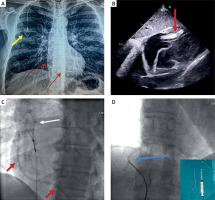

We present the case of a 52-year-old man with pancreatic cancer who had a port-a-cath implanted for chemotherapy 4 years ago and was referred to our hospital for extraction. This was an incidental finding after a routine chest X-ray. The X-ray showed detachment of the distal port-a-cath fragment which had slipped in the right ventricle (Figure 1 A). A transthoracic echocardiogram demonstrated the detached fragment floating in the right ventricle and protruding in the right atrium through the tricuspid valve (Figure 1 B).

A – Chest X-ray demonstrating the port under the skin (yellow arrow) and the detached fragment of the port-a-cath (red arrows). B – Transthoracic echocardiogram, subcostal view demonstrating the detached fragment lying in the right ventricle and protruding through the tricuspid valve in the right atrium (red arrows). C – Fluoroscopy image demonstrating the vascular snare (white arrow) and the detached fragment (red arrows). D – Fluoroscopy, the detached fragment is captured by the snare (blue arrow) + the detached fragment (around 6 cm in length) on the cath lab table

In the cardiac catheterisation laboratory, we decided to follow the loop snare proximal grab technique [1]. Access was obtained via the right femoral vein, and given that the size of most port-a-cath catheters used in our geographical area is 6 Fr, we decided to use a 12 Fr sheath that would be able to accommodate the folding of the port-a-cath fragment. The 7F Atrieve Vascular Snare Kit (ARGON Medical Devices, Dallas, TX, USA) was advanced through a 10F slittable outer guide catheter (CPS Direct Universal, St Jude Medical, CA, USA) in order to approach the detached port-a-cath fragment (Figure 1 C). Despite several attempts we were not able to capture the port-a-cath fragment because the guide catheter was quite soft and it did not have a favourable angle to help the snare to reach the detached fragment. We therefore decided to use a different guide catheter, specifically an 8F Multipurpose catheter (Launcher, Medtronic, Santa Rosa, CA, USA), which offered better support and torquability and helped us to capture the detached fragment with the snare. The guide catheter and the captured, folded port-a-cath fragment were removed through the 12 Fr femoral vein sheath without injury of the access site (Figure 1 D). The puncture site was closed by manual compression.